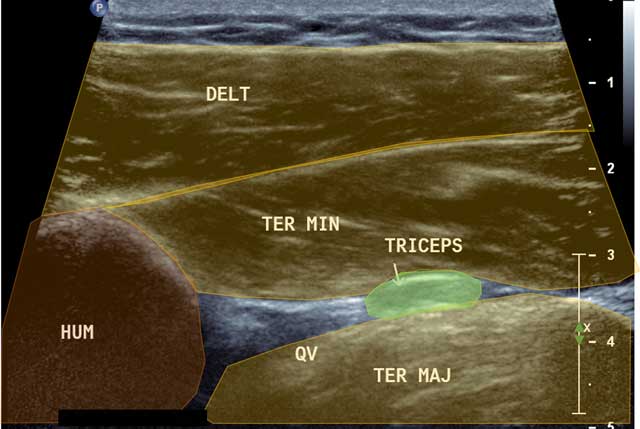

Figure 6

Focus in axial view of the quadrilateral space. HUM: Humerus, DELT: Deltoid muscle, QV: Quadrilateral Velpeau Space, Ter Maj: Teres Major, Ter Min: Teres Minor, Triceps: Tricipital muscle.